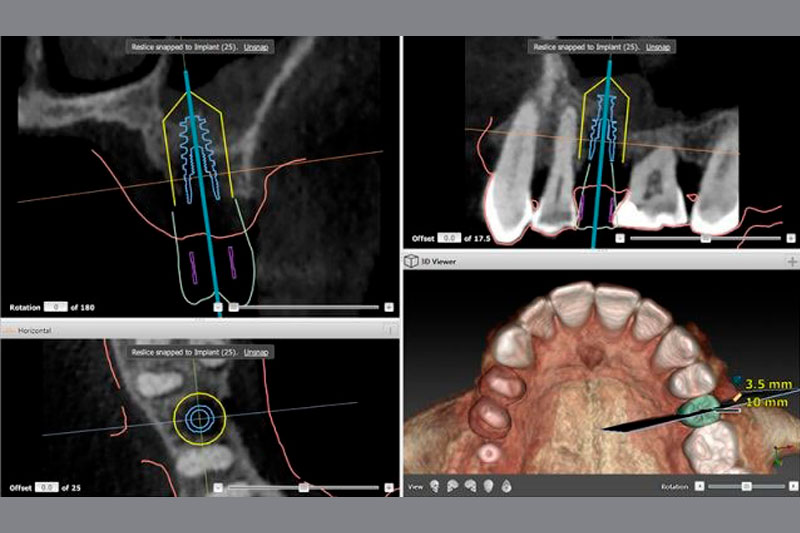

A Oliver Coll, cirurgia guiada per ordinador:

Precisió i seguretat en cada cas.

En aquells casos en què està indicat, utilitzem cirurgia guiada per ordinador. Mitjançant una planificació digital prèvia i una guia quirúrgica dissenyada a mida per a cada pacient, podem col·locar els implants amb una precisió mil·limètrica, respectant l’anatomia de cada persona. Aquesta tècnica millora la seguretat del procediment, fa la intervenció menys invasiva i afavoreix una recuperació més ràpida i còmoda.